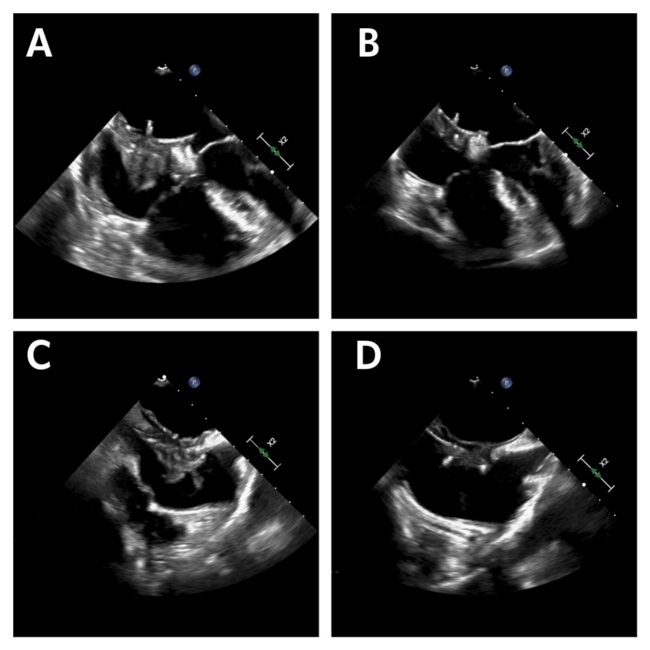

One-month follow-up revealed a thrombus measuring 1.9 x 1.5 cm that was attached to the right atrial disc of the ASD occluder device (Figure A and C). No interatrial shunt was noted with agitated saline, and no left atrial thrombus was visualized. The patient had no hypercoagulable disorders or evidence of infective endocarditis. ASA was switched to oral anticoagulation with warfarin with a target international normalized ratio (INR) of 2.0 to 3.0. TEE at 3 months showed a persistent right atrial device-related thrombus. Eighty-one mg of ASA daily was added alongside an increase in the target INR to 3.0 to 3.5. Four-month follow-up TEE demonstrated resolution of the thrombus, prompting discontinuation of warfarin (Figure B and D). There was no recurrence of thrombus formation at the 18-month follow-up.